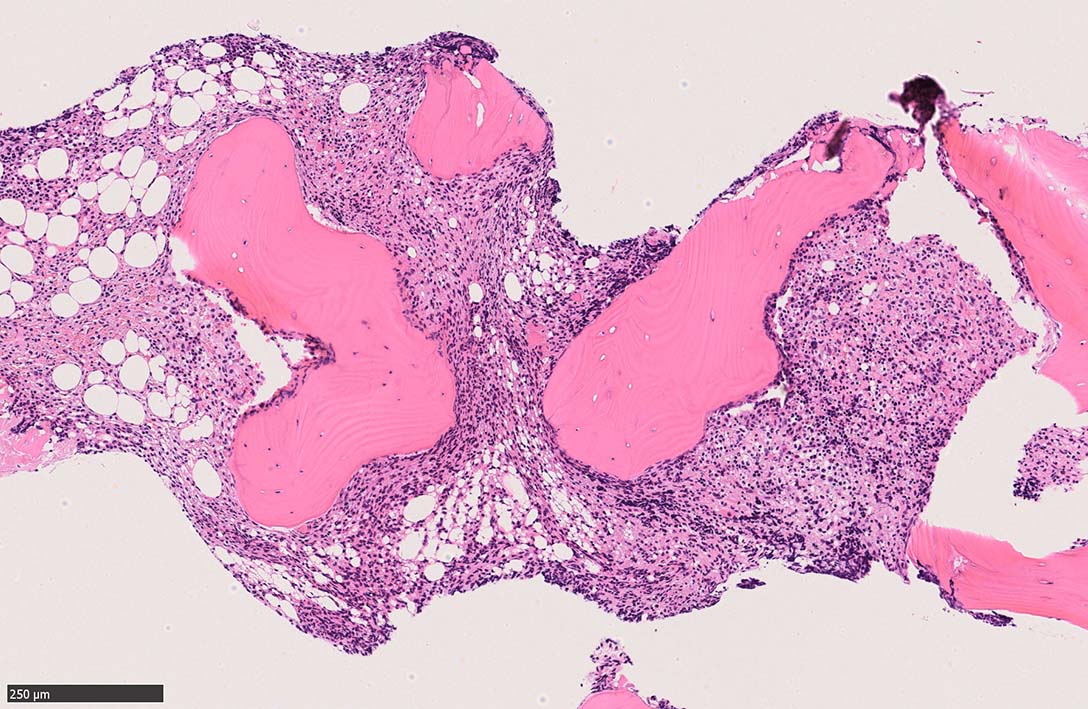

骨髄生検

bone marrow trephine biopsy: dry tapのため骨髄生検が行われる. cellularityは40-80%とhypercellular marrow. 流れのある細胞配列は線維化を疑わせる.

ASD-G 低倍率所見では赤芽球血島は幼若赤芽球の集簇巣が散在する, 顆粒球系細胞(ASDに赤く染色される)は減少,granulopoietic hypoplasiaを呈する.疎な集簇を示すmast cellsの増加がある.

ASD-G陰性の細胞がびまん性に増加しているように見える.

ASD-Giemsa陰性の細胞がシート状に増殖する. 核はクロマチン濃染, 核小体は不明瞭.類円形, 卵円形, くびれを持つ多稜形核, 長円形いびつで屈曲した核, など多彩. 細胞質は淡清色調, 広く淡明. 赤芽球血島は幼若赤芽球のみで形成される異形成像を示す. やや離れて成熟赤芽球が疎な集簇を示す.

Ag染色では, 疎な弾性線維が増生し,増殖細胞を小胞巣状に分画するいわゆる「lymphomatoid pattern」を呈する. 本例では, Mgkに異形成所見がある.